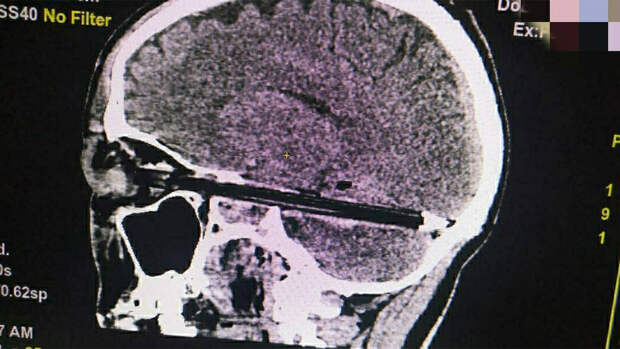

Обвиняемый заявил, что травмировал он себя сам, в состоянии нервного срыва.Впоследствии его экстренно госпитализировали с шариковой ручкой в голове. Ручка повредила ему глаз и вошла в мозг на весь диаметр полости черепа, при этом она прошла в миллиметре от важнейших сосудов и ствола головного мозга. Врачи прооперировали пострадавшего, после чего он был переведен в реанимацию. Во вторник, 9 февраля, стало известно, что пациент скончался.